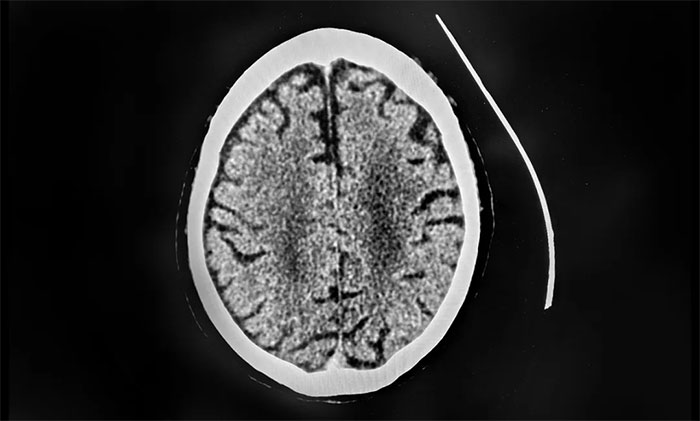

有著30多年豐富臨床經(jīng)驗(yàn)的上海藍(lán)十字腦科醫(yī)院學(xué)術(shù)副院長(zhǎng)、4A腦血管病一科主任席剛明教授指出,患者從癥狀上看懷疑顱內(nèi)靜脈竇血栓形成。急查顱腦CT平掃未示新發(fā)出血,發(fā)現(xiàn)右側(cè)橫竇、竇匯、上矢狀竇密度增高,此外,D-二聚體(檢測(cè)血栓形成的關(guān)鍵指標(biāo))達(dá)到26.21mg/L,遠(yuǎn)超正常值。

▲ CT檢查發(fā)現(xiàn)右側(cè)橫竇、竇匯、上矢狀竇密度增高